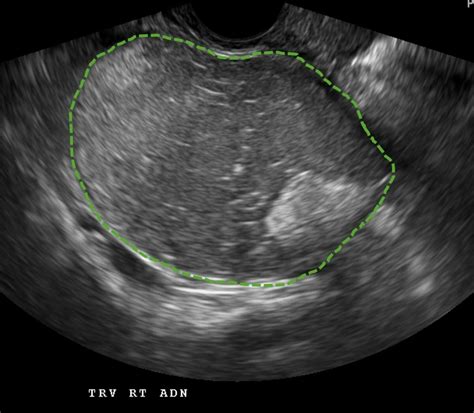

When a physician suspects a dermoid cyst ovary, they will utilize specific diagnostic tools to confirm the presence, size, and location of the mass. Imaging is the gold standard for diagnosis because the specific contents of these cysts—such as fat, calcium (teeth/bone), and fluid—have distinct appearances on scans.

Pelvic Ultrasound The primary tool to visualize the cyst and determine if it is solid or fluid-filled.